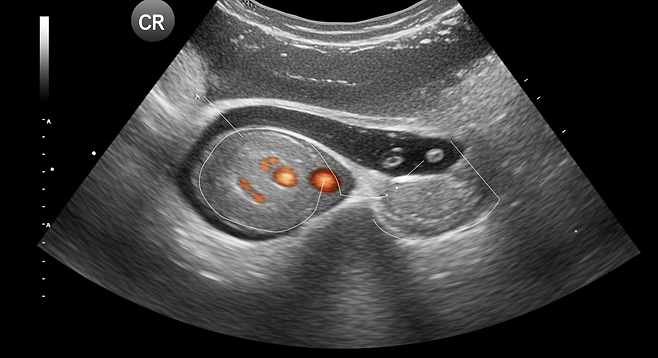

- 골반 초음파 검사 (가장 널리 이용되는 방법)